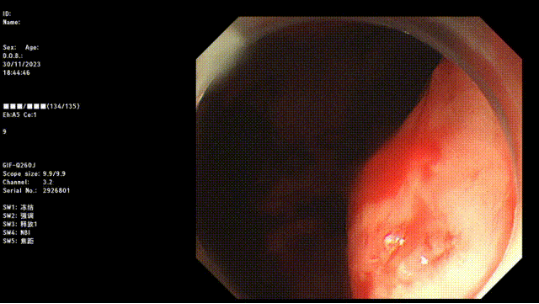

1. 内镜检查:包括胃镜、结肠镜等内镜检查技术,可以直接观察到消化道黏膜的情况,帮助医生确定出血的原因。

止血成功